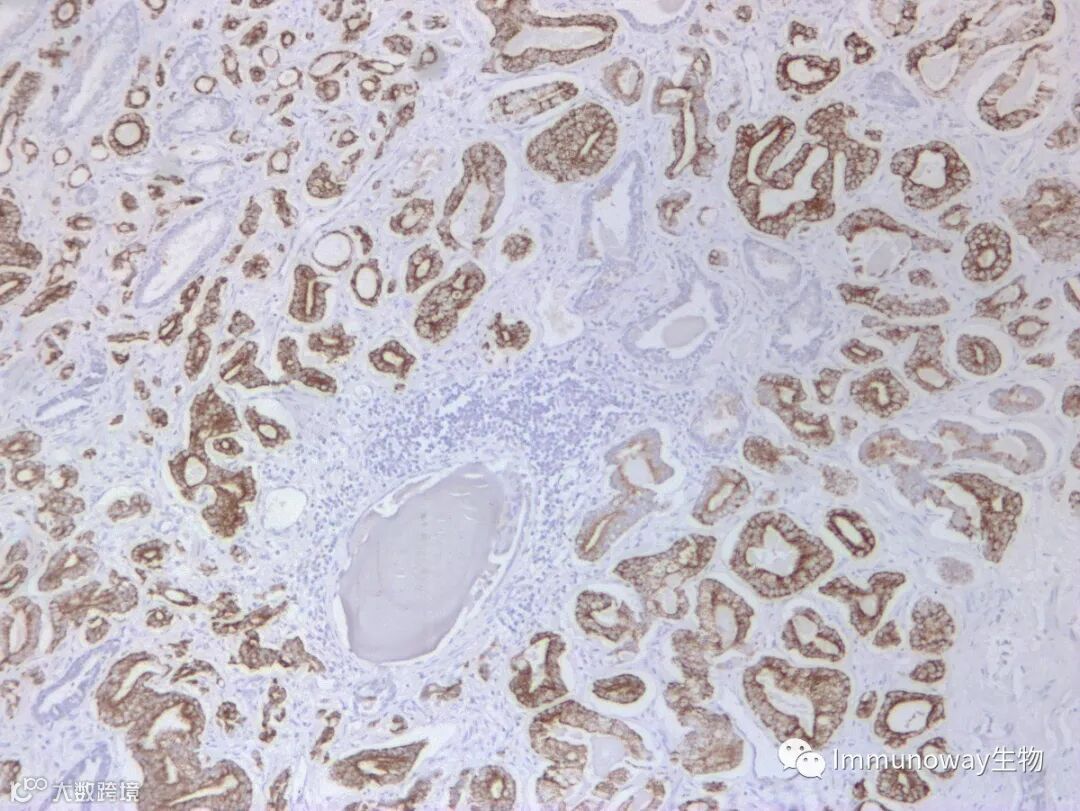

检测组织:前列腺癌组织石蜡切片

二抗:普通直接酶标记二抗

结论:结果显色癌细胞胞膜弱阳性,有背景

二抗:病理级Polymer酶标记二抗

结论:结果显色癌细胞胞膜强阳性,低背景